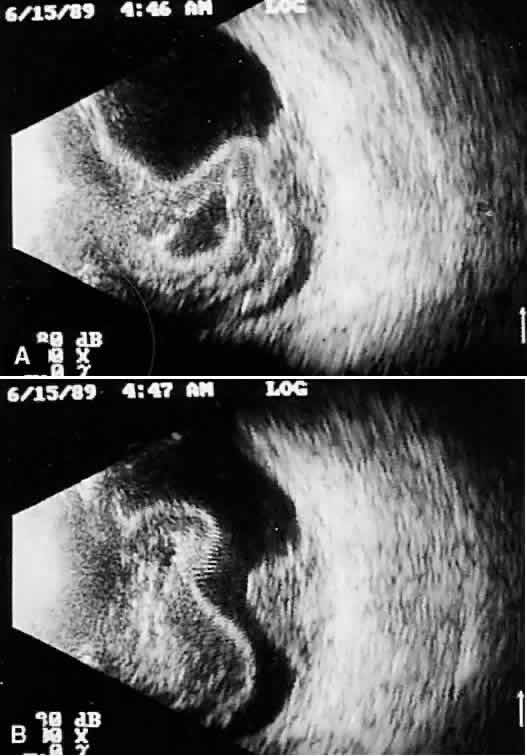

Once reflected, echoes are received, amplified, and electronically processed. They are displayed in visual format as A-scan or B-scan images. A-scan (A-mode or time-amplitude) ultrasonography is used predominantly for tissue characterization and interpretation. The horizontal axis of this display represents time or distance and is useful for linear measurements, whereas the vertical dimension reveals echo amplitude and is useful for characterizing tissues (Fig. 1). A-scan may be performed independently of B-scan. B-scan (B-mode or intensity-modulated) ultrasonography provides a cross-sectional image of the globe and orbit (Fig. 2). B-scans are used predominantly for topographic information. There are overlaps of information from A-scan and B-scan; most physicians rely on both forms for adequate ultrasound interpretation, and instruments are available that present B-scan and A-scan images simultaneously (Fig. 3). The display images are presented horizontally in contact scanning and vertically with waterbath (immersion) scanning6–8 (Fig. 4).

Fig. 4. Immersion B-scan. B. Simultaneous A-scan, vertical format. Cornea and anterior segment are seen easily with waterbath stand-off. A-scan is imaged separately to the side. (Courtesy of DJ Coleman, MD, and Sue Woods, ultrasound laboratory, New York Hospital.)